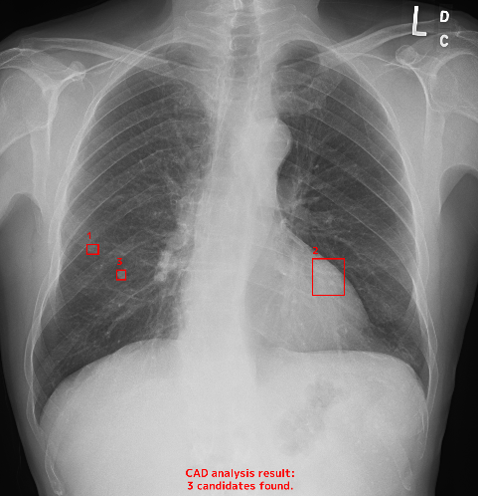

● 胸部X線 AI読影AI読影は、医用画像をAI(人工知能)が解析し、 医師の画像診断を支援する取り組みです。 診断の参考情報として活用し、より丁寧な読影につなげています。

医師とAIが連携することで、より質の高い医療の提供につなげています。 -